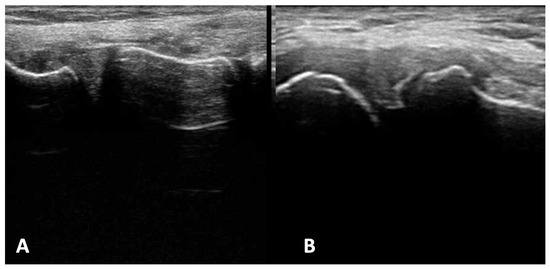

Ultrasound imaging of medial and lateral menisci involved visualization of three elements: anterior horn, meniscal body, and posterior horn. With the patient in the supine position, the transducer was applied along the sagittal plane transversely to the longitudinal meniscal axis.

Projections longitudinal to the long axis of the meniscus were also used in the imaging techniques. They may be useful in the diagnostics of marginal or pericapsular zone injuries. Longitudinal cross-section of the meniscus is much less frequently used in ultrasound imaging compared to the transverse cross-section.